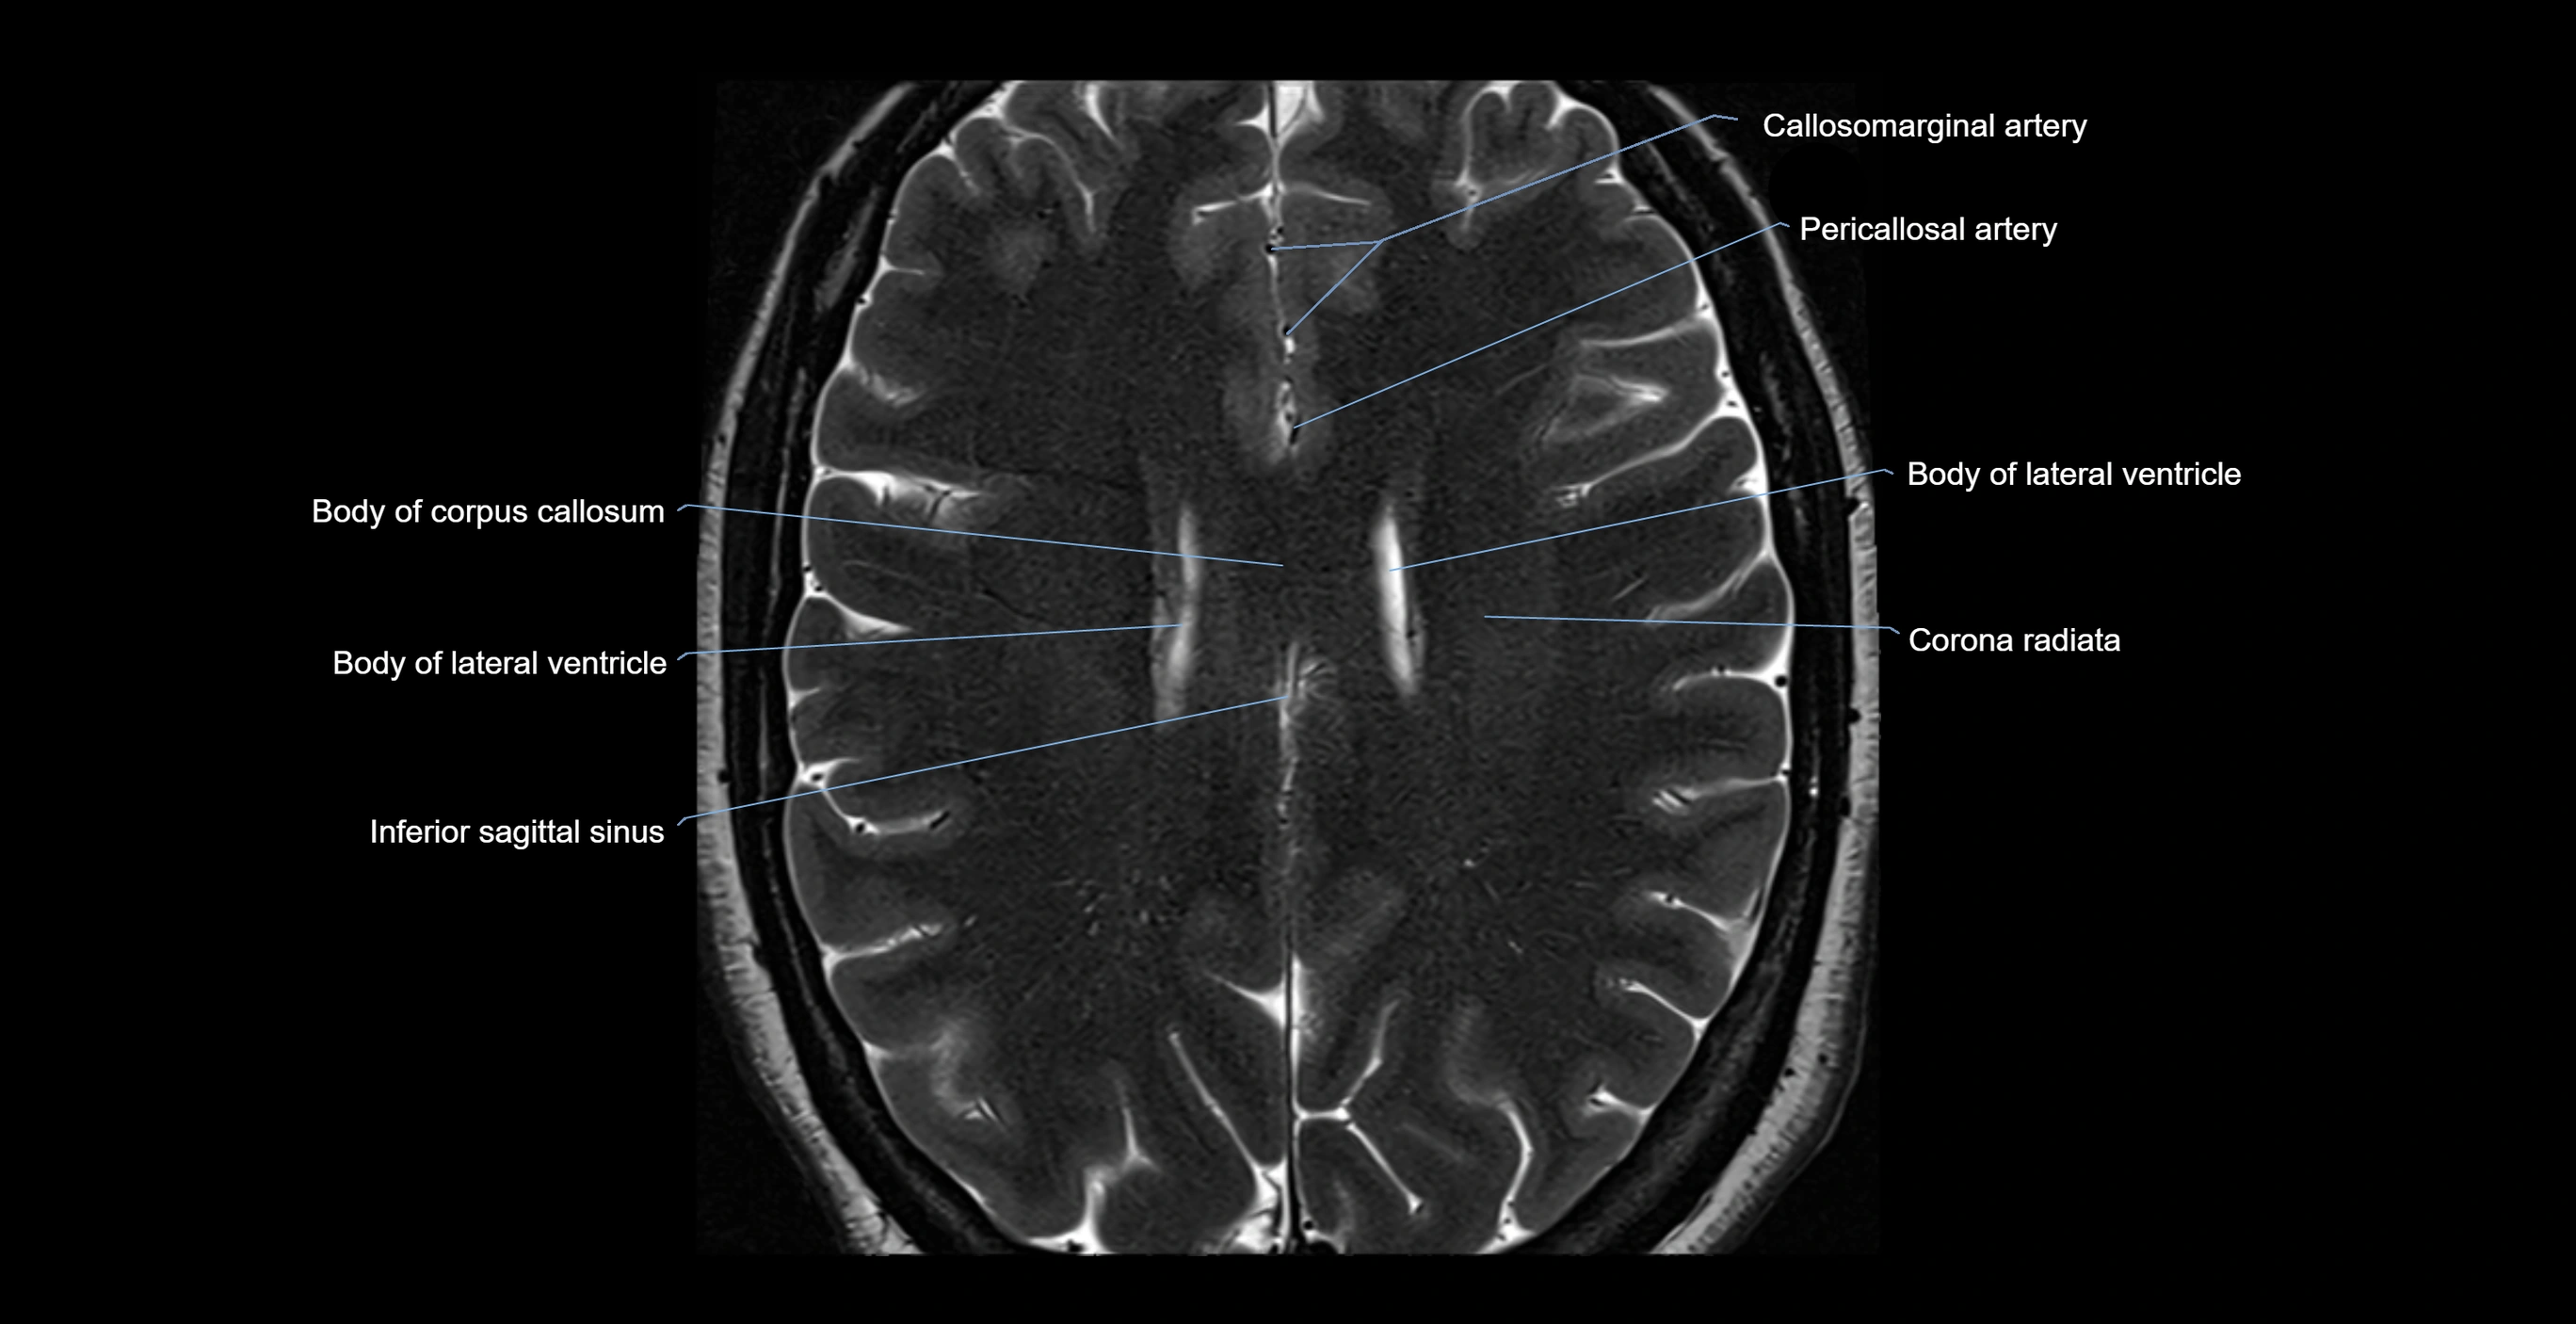

- Body of corpus callosum

- Body of lateral ventricle

- Callosomarginal artery

- Corona radiata

- Inferior sagittal sinus

- Pericallosal artery